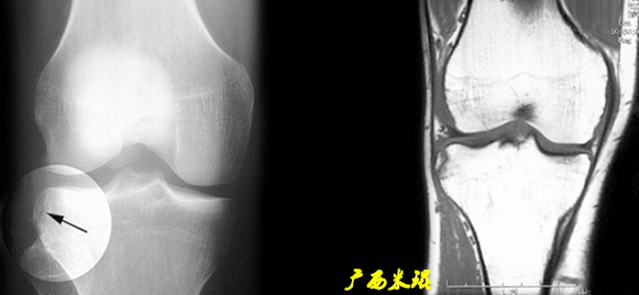

5)Segond骨折:

-

胫骨平台前外侧撕脱骨折(胫骨平台腓骨尖上方,关节线下方的撕脱骨折),多因为下肢过度内翻加内旋暴力所致。

骨折本身无特殊治疗,但其强烈提示ACL损伤(75–100%)。